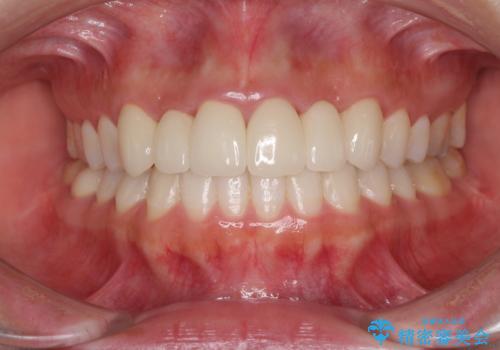

強い咬合力で歯が割れる 奥歯を1DAYインプラントで短期間治療

- 奥歯が割れてしまい、抜歯が必要となった患者様です。

以前にも歯が割れてインプラント治療を行いましたが、抜歯してからインプラント埋入→仮歯装着までに半年以上を要し、その間に残された歯への負担が大きくなり、左右反対側のセラミッククラウンが破折したことがありました。

そのため、当院に新しく導入した手法により、抜歯をした日にインプラントを埋入し、そのままを仮歯を装着することで、他の歯への負担を軽減する計画を立てました。

インプラント埋入時に植立具合の安定性を測定したところ、十分な数値が得られたため、速やかに仮歯を装着して咬合回復をさせることができました。

抜歯を含めた外科処置を1回に抑えることができ、あっという間に治療を終えることができました。